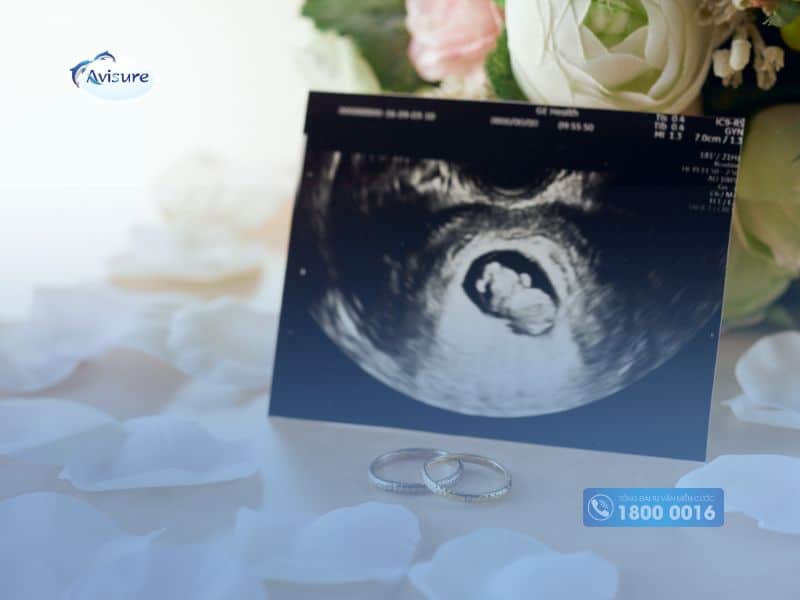

Siêu âm là phương pháp phổ biến nhất hiện nay để xác định giới tính thai nhi. Tuy nhiên, siêu âm xác định giới tính trai hay gái chỉ được thực hiện từ tuần 12 - 16 trở đi, chưa thể xác định được giới tính ở tuần 7 thai kỳ. Vì, thai 7 tuần chưa phát triển rõ ràng bộ phận sinh dục để nhận biết trai hay gái qua hình ảnh siêu âm. Bác sĩ chỉ có thể quan sát được tim thai và một số đặc điểm phát triển của cơ thể bé mà chưa thể nhận biết rõ giới tính.

Siêu âm là phương pháp khá an toàn, không gây xâm lấn, độ chính xác cao và còn theo dõi được sự phát triển đều đặn của thai nhi. Vì vậy, mẹ nên thực hiện siêu âm thai định kỳ để biết thai nhi khỏe mạnh trong bụng. Thay vì dựa vào nhịp tim thai 7 tuần biết trai hay gái, mẹ nên đợi đến các mốc siêu âm quan trọng để kiểm tra hoặc kết hợp với xét nghiệm NIPT để dự đoán giới tính thai nhi.